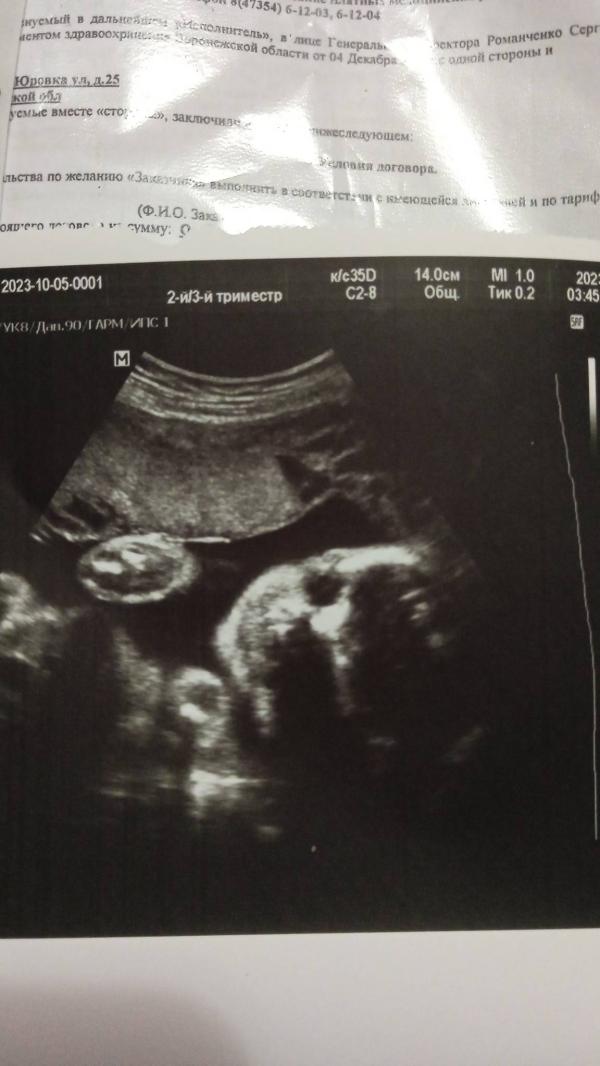

Сынок махал мне ручкой на УЗИ, которое быдо две недели назад 🙏интересно сколько он сейчас весит? Мамульки, а сколько весил ваш малыш на третьем скрининге? 🌷